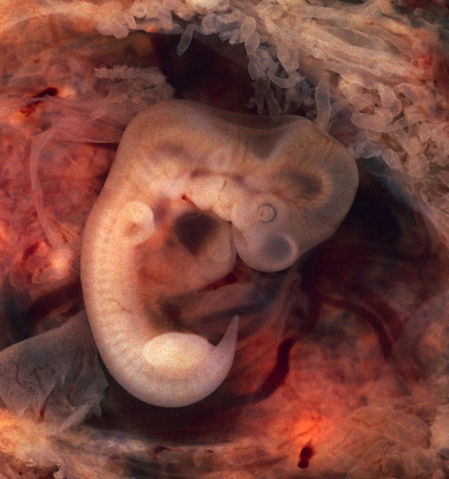

Description Human Embryo (7th week of pregnancy, 5th week p.o.)

This photo of an opened oviduct with an ectopic pregnancy features a spectacularly well preserved 10-millimeter embryo. It is uncommon to see any embryo at all in an ectopic, and for one to be this well preserved (and undisturbed by the prosector's knife) is quite unusual.

Even an embryo this tiny shows very distinct anatomic features, including tail, limb buds, heart (which actually protrudes from the chest), eye cups, cornea/lens, brain, and prominent segmentation into somites. The gestational sac is surrounded by myriad chorionic villi resembling elongated party balloons. This embryo is about five weeks old (or seven weeks in the biologically misleading but eminently practical dating system used in obstetrics).

The photo was taken on Kodak Elite 200 slide film, with a Minolta X-370 camera and 100mm f/4 Rokkor bellows lens at near-full extension. The formalin-fixed specimen was immersed in tap-water and pinned to a tray lined with black velvet. The exposure was 1/4 second at f/8.